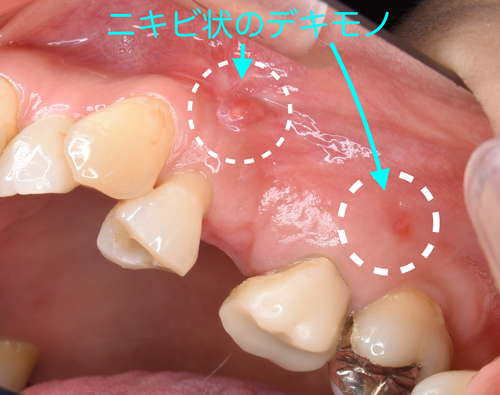

奈良の歯科医で型取りをしたまま治療放置。根の先には黒い影が発生して、大きな腫瘍が生じていると思われました。

抜歯直後の状態。激痛の原因となる腫瘍が摘出されました。

更に奥には横向きに生えている親知らずの歯を確認。

これも続けて抜歯しました。